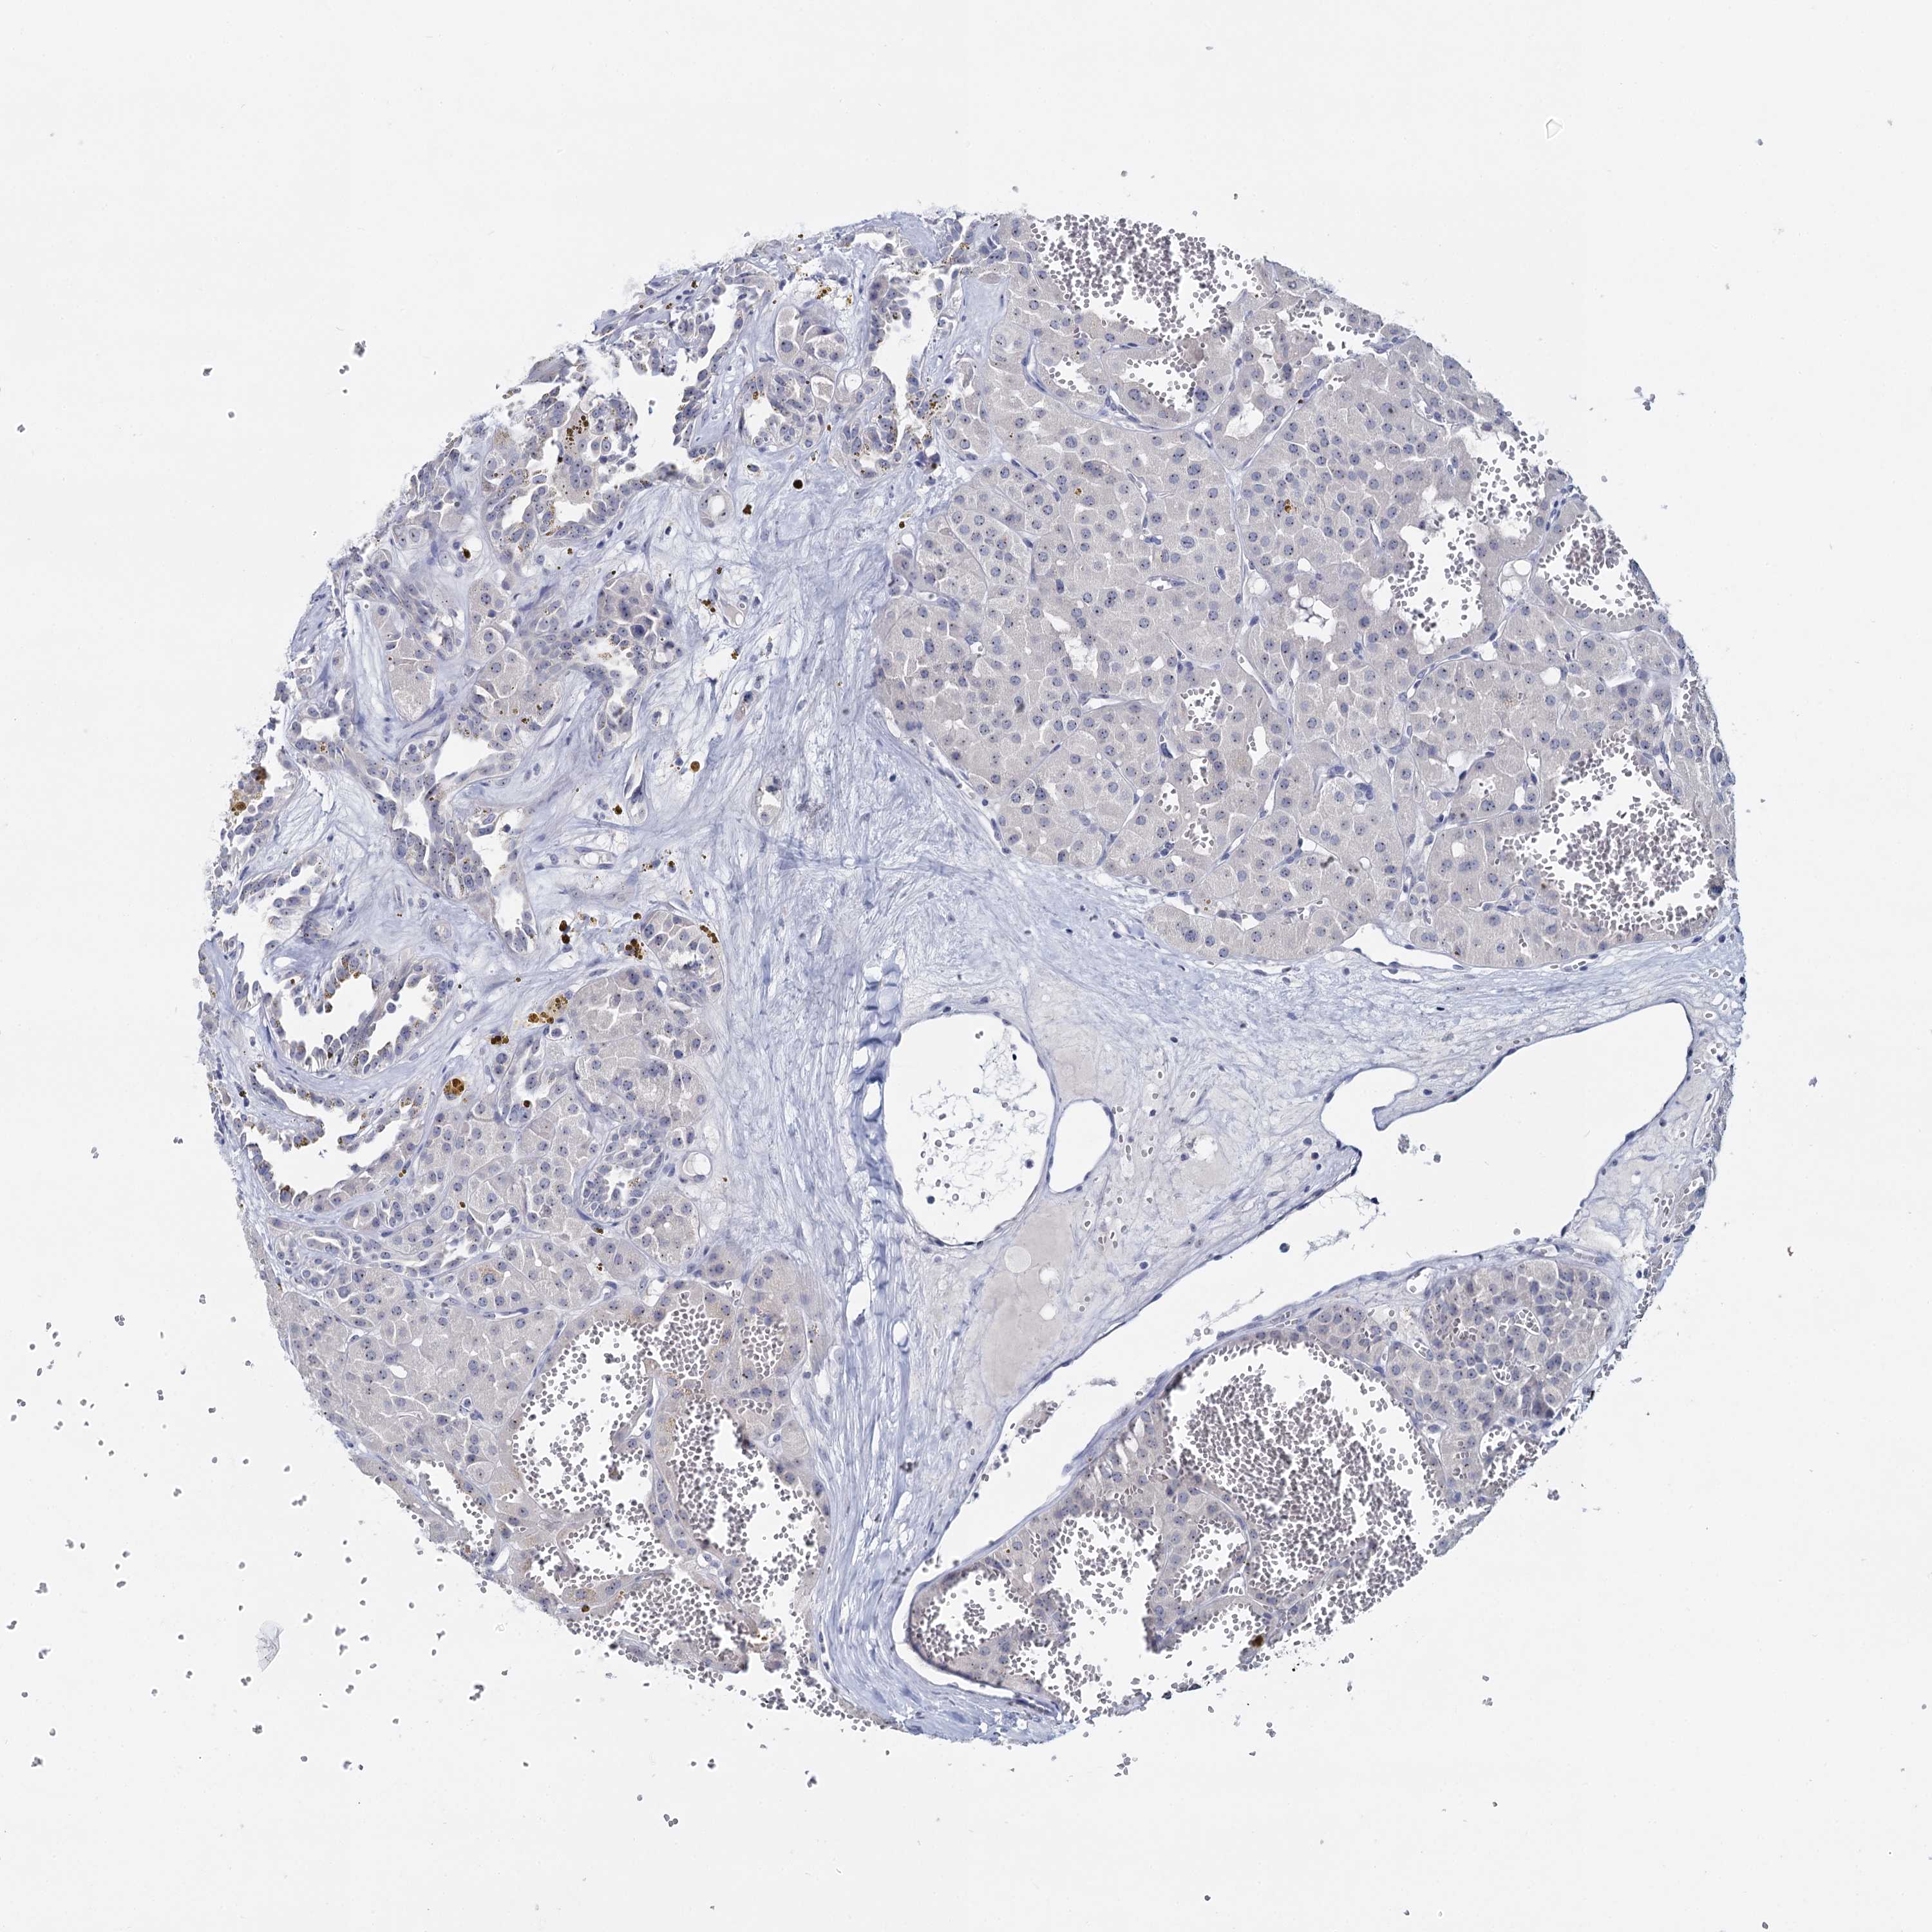

KIDNEY RENAL CLEAR CELL CARCINOMA (VALIDATION) - Interactive survival scatter ploti

The Survival Scatter plot shows the clinical status (i.e. dead or alive) for all individuals in the patient cohort, based on the same data that underlies the corresponding Kaplan-Meier plots. Patients that are alive at last time for follow-up are shown in blue and patients who have died during the study are shown in red.

The x-axis shows the expression levels (FPKM) of the investigated gene in the tumor tissue at the time of diagnosis. The y-axis shows the follow-up time after diagnosis (years). Both axes are complimented with kernel density curves demonstrating the data density over the axes. The top density plot shows the expression levels (FPKM) distribution among dead (red) and alive patients (blue). The right density plot shows the data density of the survived years of dead patients with high and low expression levels respectively, stratified using the cutoff indicated by the vertical dashed line through the Survival Scatter plot. This cutoff is automatically defined based on the FPKM cutoff that minimizes the p-score. The cutoff can be changed by dragging the vertical line or by entering a cutoff value in the square labeled "Current cut-off".

Under the Survival Scatter plot the p-score landscape (black curve; left axis) is shown together with dead median separation (red curve; right axis). Dead median separation is the difference in median mRNA expression between patients who have died with high and low expression, respectively. It is calculated as follows: median FPKM expression of dead patients with high expression - median FPKM expression of dead patients with low expression. This is intended to aid the user in visually exploring custom cutoffs and the associated p-scores and dead median separation.

Individual patient data is displayed and can be filtered by clicking on one or more of the category buttons on the top of the page. Categories describing expression level and patient information include: high, low, alive, dead, female, male and tumor stages. The scale of the x-axis can be toggled between linear and log-scale by clicking on the "x log" button. Mouse-over function shows TCGA ID, patient information and mRNA expression (FPKM) for each patient.

& Survival analysisi

Kaplan-Meier plots summarize results from analysis of correlation between mRNA expression level and patient survival. Patients were divided based on level of expression into one of the two groups "low" (under cut off) or "high" (over cut off). X-axis shows time for survival (years) and y-axis shows the probability of survival, where 1.0 corresponds to 100 percent.

SFN is not prognostic in Kidney Renal Clear Cell Carcinoma (validation)

Best expression cut offi

Based on the FPKM value of each gene, patients were classified into two groups and association between prognosis (survival) and gene expression (FPKM) was examined. The best expression cut-off refers the FPKM value that yields maximal difference with regard to survival between the two groups at the lowest log-rank P-value. Best expression cut-off was selected based on survival analysis .

When clicking on this number, the vertical dashed line indicating cut-off, the interactive survival plot, and the Kaplan-Meier curve will be adjusted to show results based on the best expression cut-off.

: 7.25

P scorei

Log-rank P value for Kaplan-Meier plot showing results from analysis of correlation between mRNA expression level and patient survival.

N/A

TCGA RNA samplesi

RNA-seq data is reported as average FPKM (number Fragments Per Kilobase of exon per Million reads), generated by the The Cancer Genome Atlas (TCGA) .

Normal distribution across the dataset is visualized with box plots, shown as median and 25th and 75th percentiles. Points are displayed as outliers if they are above or below 1.5 times the interquartile range. FPKM values of the individual samples are presented next to the box plot.

Average pTPM 6.6

Number of samples 100